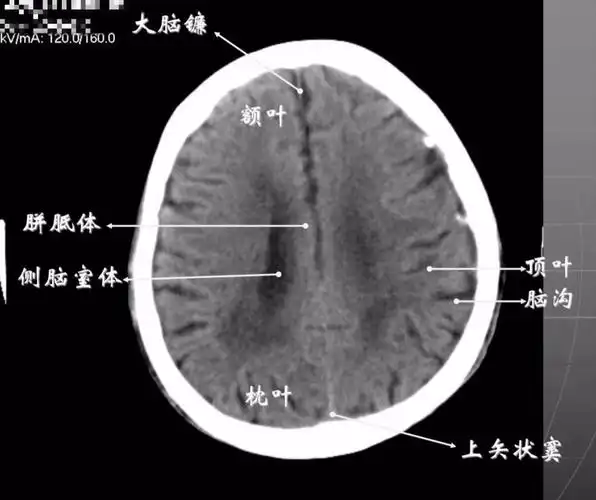

读懂头颅ct并不难教你成为读片小能手